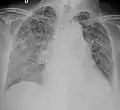

A case of miliary tuberculosis in an 82-year-old woman:

X-ray, 13 days after onset, showing bilateral interstitial infiltrates

X-ray, 22 days after onset, showing extensive bilateral reticulo-nodular infiltrates